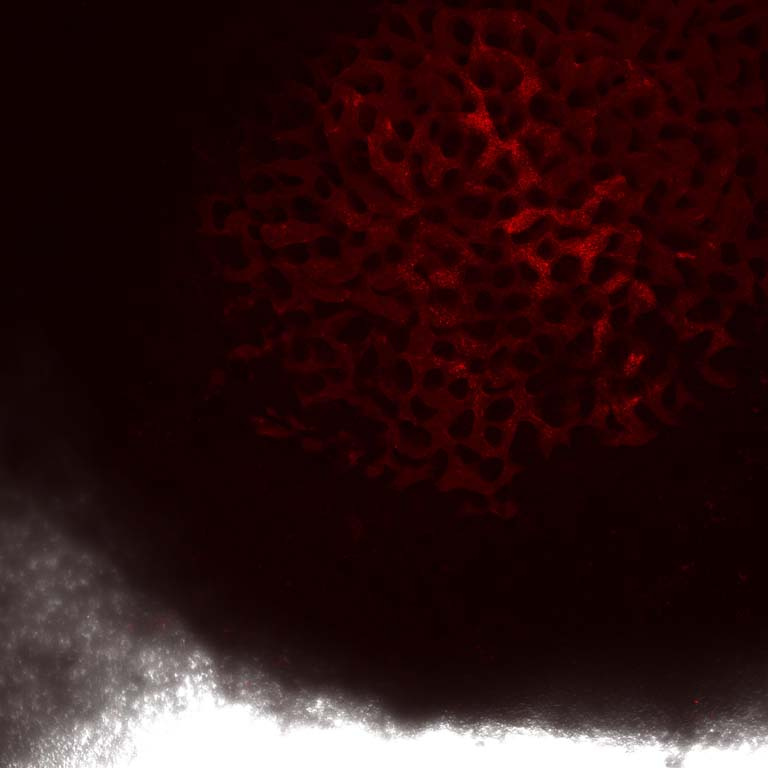

Here we see images of gastrointestinal surfaces (Stomach and Small Intestine), where the cell surface structure has been modified to allow for improved drug uptake. The surface modification has here been made visible by a fluorescent dye, allowing us to study which parts of the GI tract have successfully been converted.